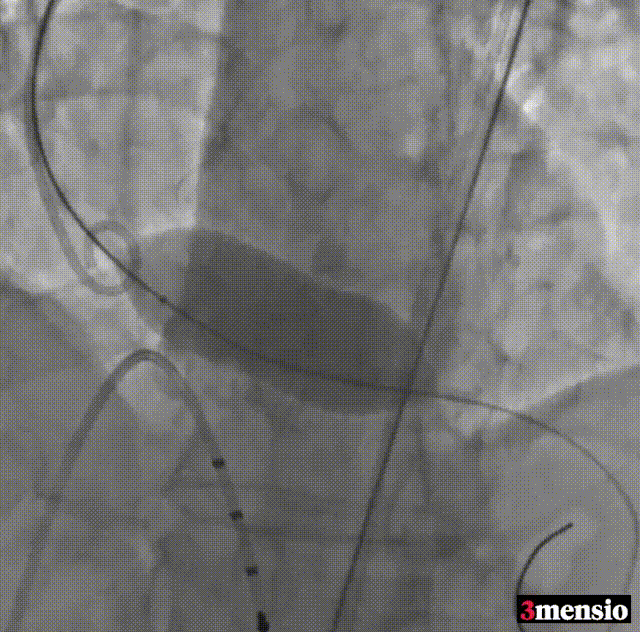

第一次瓣膜释放,瓣膜回跳

回收瓣膜

第二次瓣膜释放,工作位评估